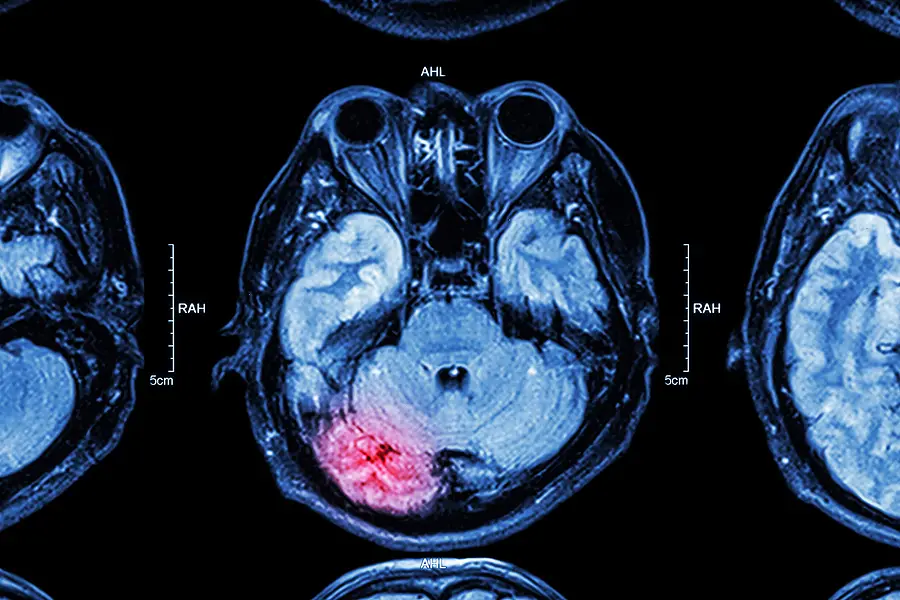

MRI of damaged brain

Lawsuits filed in California seek potential class-action damages from Dow Chemical and its successor company over a widely used bug killer linked to brain damage in children.

Exposure to the chemical, either direct or secondhand, can cause serious issues, such as neurological damage.

In each case, the plaintiffs are parents suing on behalf of their children who suffer from severe neurological damage that the lawsuits blame on exposure to the chemical while they were in the womb or when they were very young.

Researchers have also found that prenatal exposure to chlorpyrifos is linked to lower birth weight, reduced IQ, loss of working memory, attention disorders, and delayed motor development.